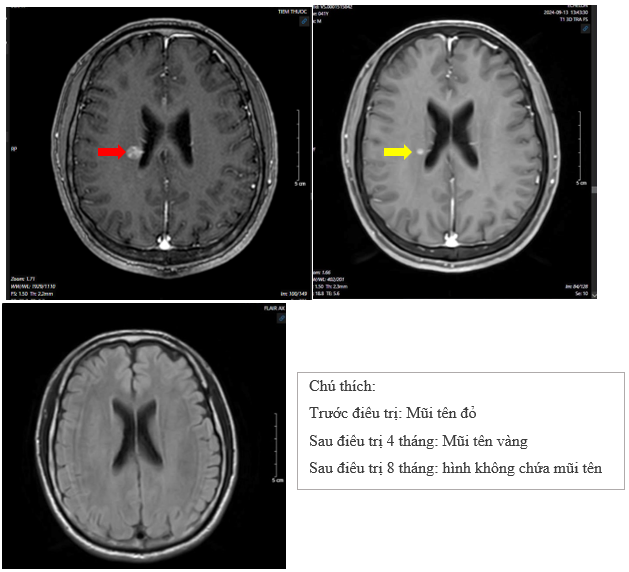

- Chụp cộng hưởng từ sọ não:

Hình 5: So sánh phim chụp cộng hưởng từ sọ não trước điều trị so với phim chụp sau điều trị 4 tháng:  kích thước  khối u não cạnh não thất bên phải giảm từ 11mm xuống 5 mm. Phim chụp sau điều trị 8 tháng (hình không chứa mũi tên), không thấy khối u bất thường trên phim cộng hưởng từ sọ não.